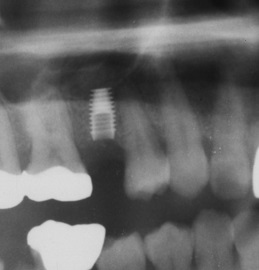

上から手術前、手術直後、術後4年のレントゲン写真です。ソケットリフトしてありますが骨補填材はBio-ossです。リフトしたところは完全に骨になっています。Bio-ossは世界標準の骨補填材で世界で一番使われています。

埋入してあるインプラントは4.5mm×8mmLのintegra-Tiのもので、このintegra-Tiというラインは表面がチタンのもので、ブラスト処理されていません。現在はこのラインは廃止されIntegra-CPというHAでブラスト処理されたものだけの販売となっています。

Integra-CPはチタンの表面にHAの粉末が少し残っています。が、埋入後3か月で吸収されてなくなります。HAcoatedインプラントとは違いますから間違えないでくださいね。